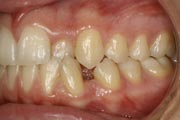

Crowding

Before